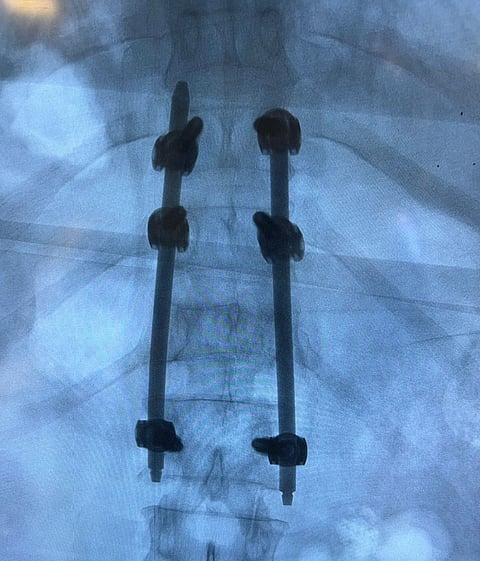

وفي العملية الأخرى، قام فريق طبي بالمجمع بتثبيت كسر غير مستقر بالفقرة الثانية عشرة، لرجل يبلغ من العمر 63 عاماً، حيث أصيب بعد تعرضه للسقوط، وتسبب ذلك في تعرضه للكسر مع تحدّب بزاوية 20.9.

وأجريت العملية بطريقة التدخل المحدود من خلال فتحات صغيره بالظهر دون الحاجة لفتح الظهر بالطريقة التقليدية، حيث تم تثبيت الكسر وتعديل التحدب وغادر المصاب المجمع بصحة جيّدة.